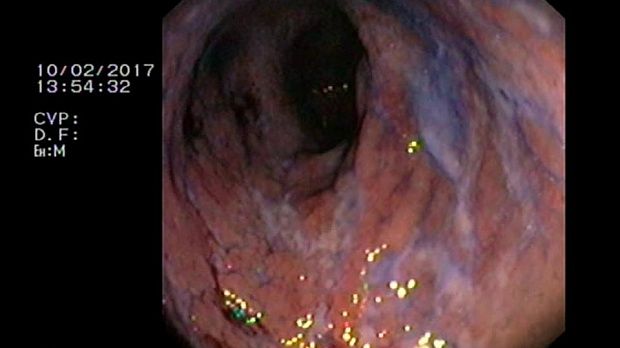

2 мл ( это мин сум, а мы делаем до 10 мл 3% перекись+200 мл физ раствора